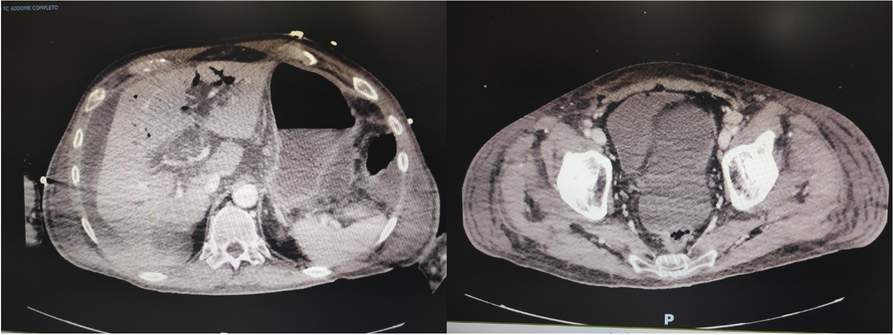

A few hours after the admission in ICU he reported a blunt abdominal pain, mainly on the right side, nausea and the exams showed increased amylase levels, urologists excluded any surgical involvement of pancreatic tissue and suspected a transient sphincter of Oddi dysfunction [3]. After one night in ICU he was transferred to the urology ward due to his clinical stability, even though Amylase peaked at 2340 U/l. Two days later abdominal pain increased to severe, with characteristics of peritonism and increased inflammatory markers. An abdomen-thorax CT scan revealed acute pancreatitis (AP) (Figure 1) and he was transferred to ICU. He started a standard treatment for acute pancreatitis and antibiotic therapy [4].

On postoperative day nine, due to general deterioration of clinical conditions and further anemization that required blood transfusion, he underwent an emergency laparotomy, in which propofol was not used as an anesthetic drug, that found a completely necrotic pancreas. The following day he faced a multi organ failure (MOF) which rapidly led to death. Consent to publish the case report was accorded by the family.

Acute pancreatitis (AP) Is a complex and severe disease with a high mortality rate [4]. Propofol, is a common anesthetic drug which is widely used in daily practice for sedations and general anesthesia [5], few cases of Propofol Induced AP have been published, in which the diagnosis has been made excluding more common causes [6].

In fact, Propofol is listed as a possible cause of AP, class Ib, based on the classification of Badalov et al. [7]. Following the scheme proposed by the systematic review by Haffar et al for Propofol induced AP [6] we could confirm that our hypothesis is plausible. He satisfied the American College of Gastroenterology criteria for AP [8,9] and it is classified as severe acute pancreatitis according to the Revised Atlanta Classification with peripancreatic necrotic fluid collection [10]. Marshall score [11] after admission was two and Naranjo et al [12] probability scale for drug adverse reaction was three, meaning that the adverse reaction is possible. Latence according to Badalov et al [7] has been short or intermediate. Exclusion of other plausible causes, timing of pancreatitis symptoms and previous cases in literature support our hypothesis of propofol induced pancreatitis.